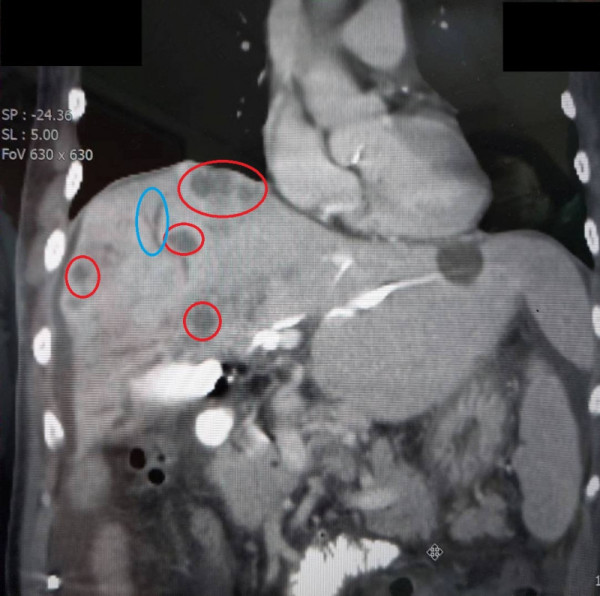

經急診檢查發現,其肝功能及黃疸指數(即血液中膽紅素濃度情況)嚴重升高,而且肝臟滿佈腫瘤,肝內膽管和總膽管異常擴張,肺部還疑似有轉移性腫瘤,最終確診罹患膽管癌末期。